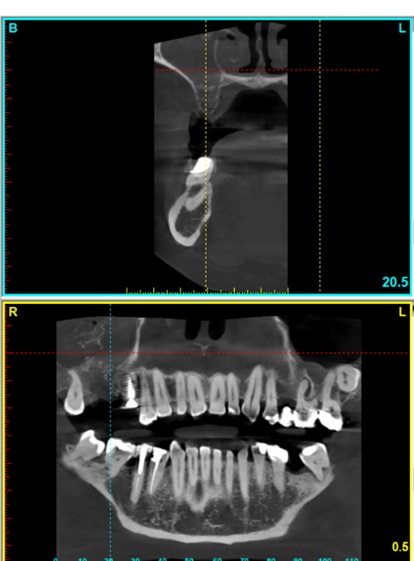

The study aims to present the location and course of the posterior superior alveolar artery (PSAA) using cone beam computed tomography (C.B.C.T.) imaging, which is considered as a valuable part for treatment planning in sinus augmentation procedures for dental implant treatment.

Data was extracted from included C.B.C.T. images using implant planning software and entered on Microsoft Excel and SPSS for statistical analysis. For each radiograph measurements were taken on premolar and molar region to determine the location of PSAA as being extraosseous or intraosseous. The distance of the artery from the floor of the sinus was also measured.

The study included 56 radiographic images. 44 view of right and left maxillary sinus satisfied the inclusion criteria. Each sinus had 2 points of measurements, giving total of 176 sites. The average distance of PSAA was 11.1 from the floor of the maxillary sinus and the median was 10.5mm. The PSAA was extraosseous in most instances with 57% of the total sample.

The location of the PSAA can be mostly in extraosseous site. The artery might also move from extraosseous to intraosseous location, or Vise versa, during its course as it travel from the molar to premolar area. Correct identification during planning of sinus lift procedures can help in avoiding accidental trauma during surgery.